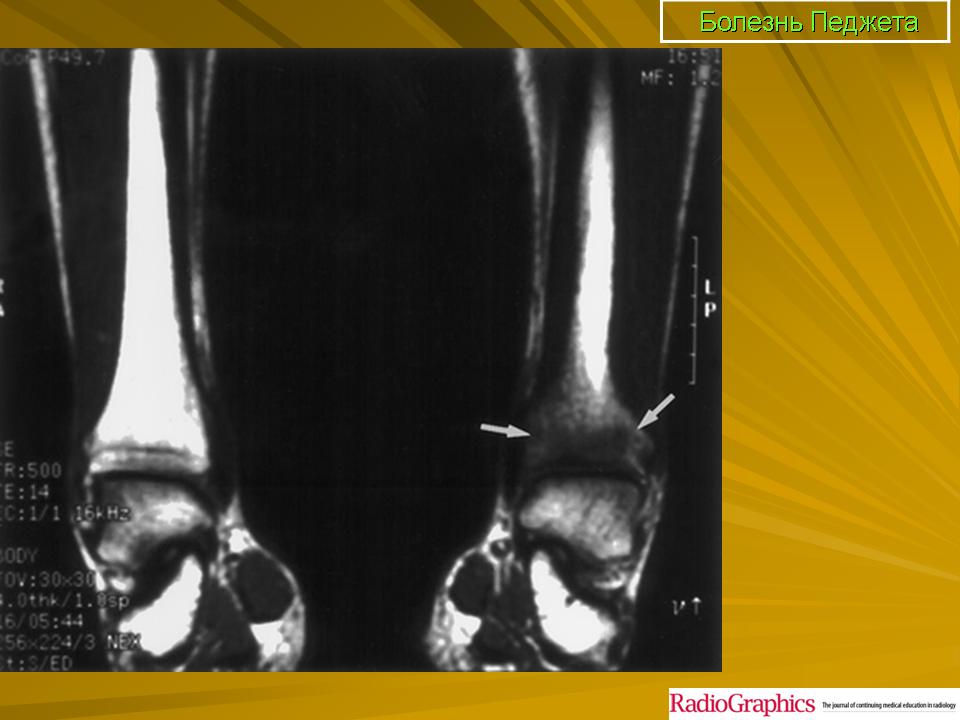

Педжета болезнь 2. +

Педжета болезнь 2.

Принято различать три фазы развития П. б.: очаговая интенсивная резорбция кости (остеолитическая, или деструктивная, фаза), смешанная фаза, когда наряду с рассасыванием кости идут процессы новообразования ее, и остеобластическая, или склеротическая, фаза с образованием типичных мозаичных структур.